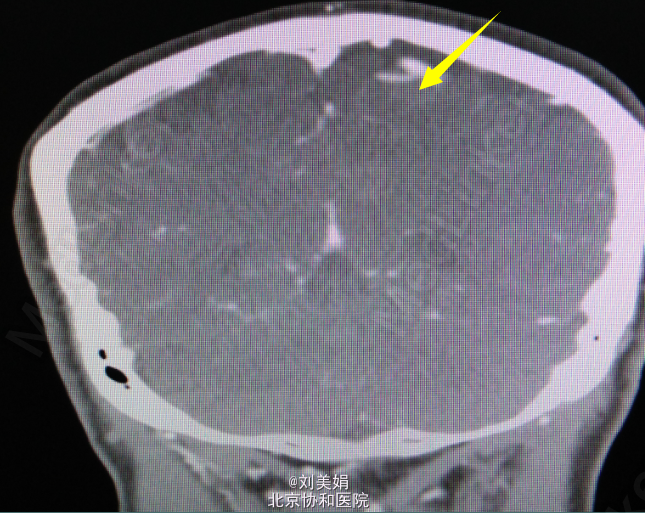

头增强CT:平扫图象显示:左侧顶部见一圆形略高密度影,边缘光整,边界清晰,大小约28.2mm×23.7mm,CT 值 68.2Hu,其内未见钙化,周围脑回受压、塌陷,脑室系统无扩大,脑沟裂未见增宽。中线结构未见明显移位。 增强图象显示:病灶明显均匀强化。CT 值为 92Hu,密度均匀,边缘清晰。右侧筛窦密度增高。

左顶部颅内占位性病变 神经导航下开颅窦旁脑膜瘤切除术